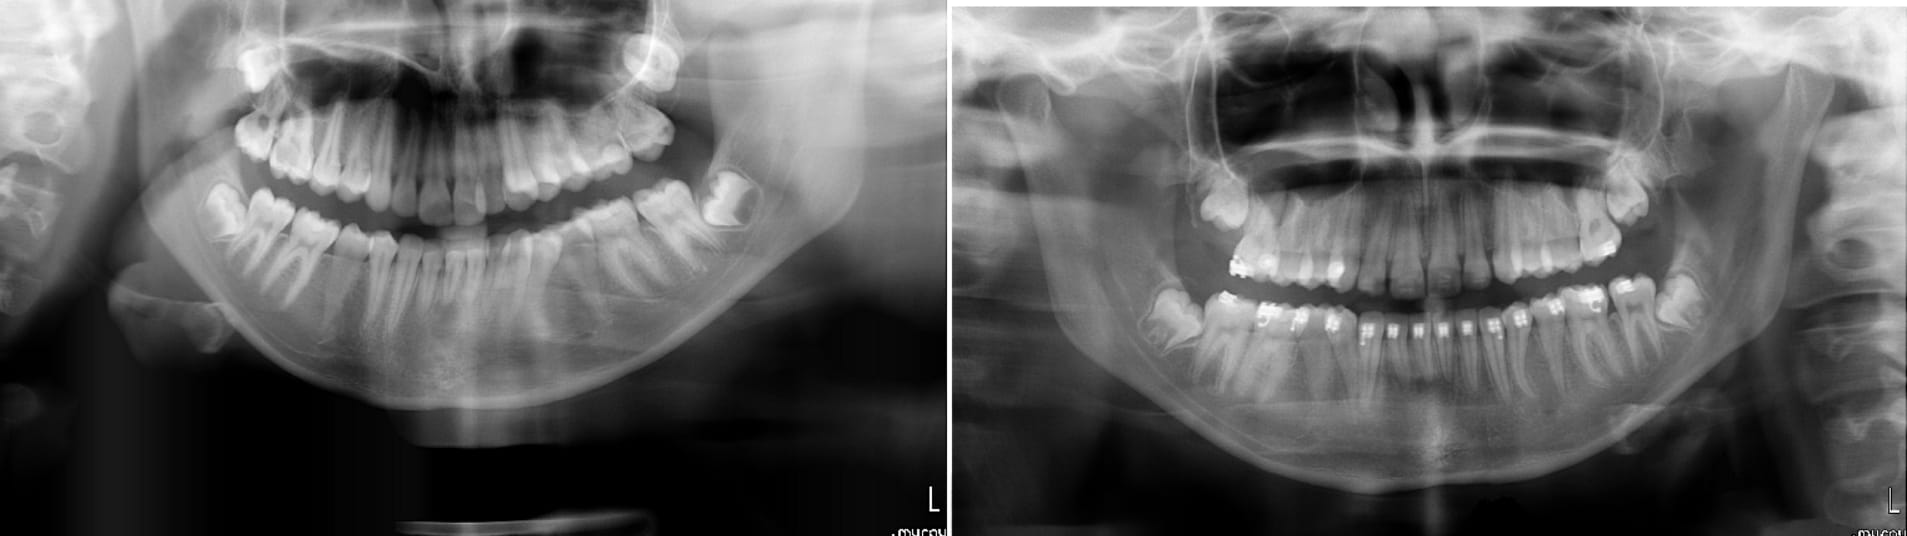

J'aurais besoin de votre avis éclairé dans la gestion de cet édentement 16 17.

La 18 est mésialée et regarde un peu en vestibulaire.

J'ai extrait la 16 suite à une fracture de racines et une infection paro.

Et maintenant se pose le problème du replacement de 16 et 17.

Que faire:

1) implant 16 et on laisse le diastème 16 / 18

2) extraction de 18 et un bridge 16 17 18 sur 2 implants 16 18.

Pour moi la 18 est loin d'être saine : carie, pb paro en mésial, version mésiale. Tout à fait justifié d'extraire cette 18. L'ortho sur une 18 ca frise le surtraitement (sans oublier que c'est très loin d'être évident) je pense pas que beaucoup de patients acceptent de l'ortho ici.